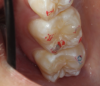

Fig 1. Point of first contact.

Figure 1

After centric relation is found, the point of first contact must be determined. The point of first contact may be a keystone tooth, but not everyone has a keystone tooth. The point of first contact needs to be marked, but not necessarily physically. In Figure 1, showing teeth Nos. 2 and 3, the point of first contact is on the mesiolingual cusp of No. 2, which has the strongest blue mark. There is also a slight mark on the distal buccal cusp of tooth No. 3. When the jaw is in centric relation, the point or coincident points of first contact are called centric occlusion. Centric relation is a joint position and is found independent of tooth contact; the joint is centered and teeth do not need to touch if centric relation is in the joint space. When the opposing teeth come together in the joint space, the term is centric occlusion.1